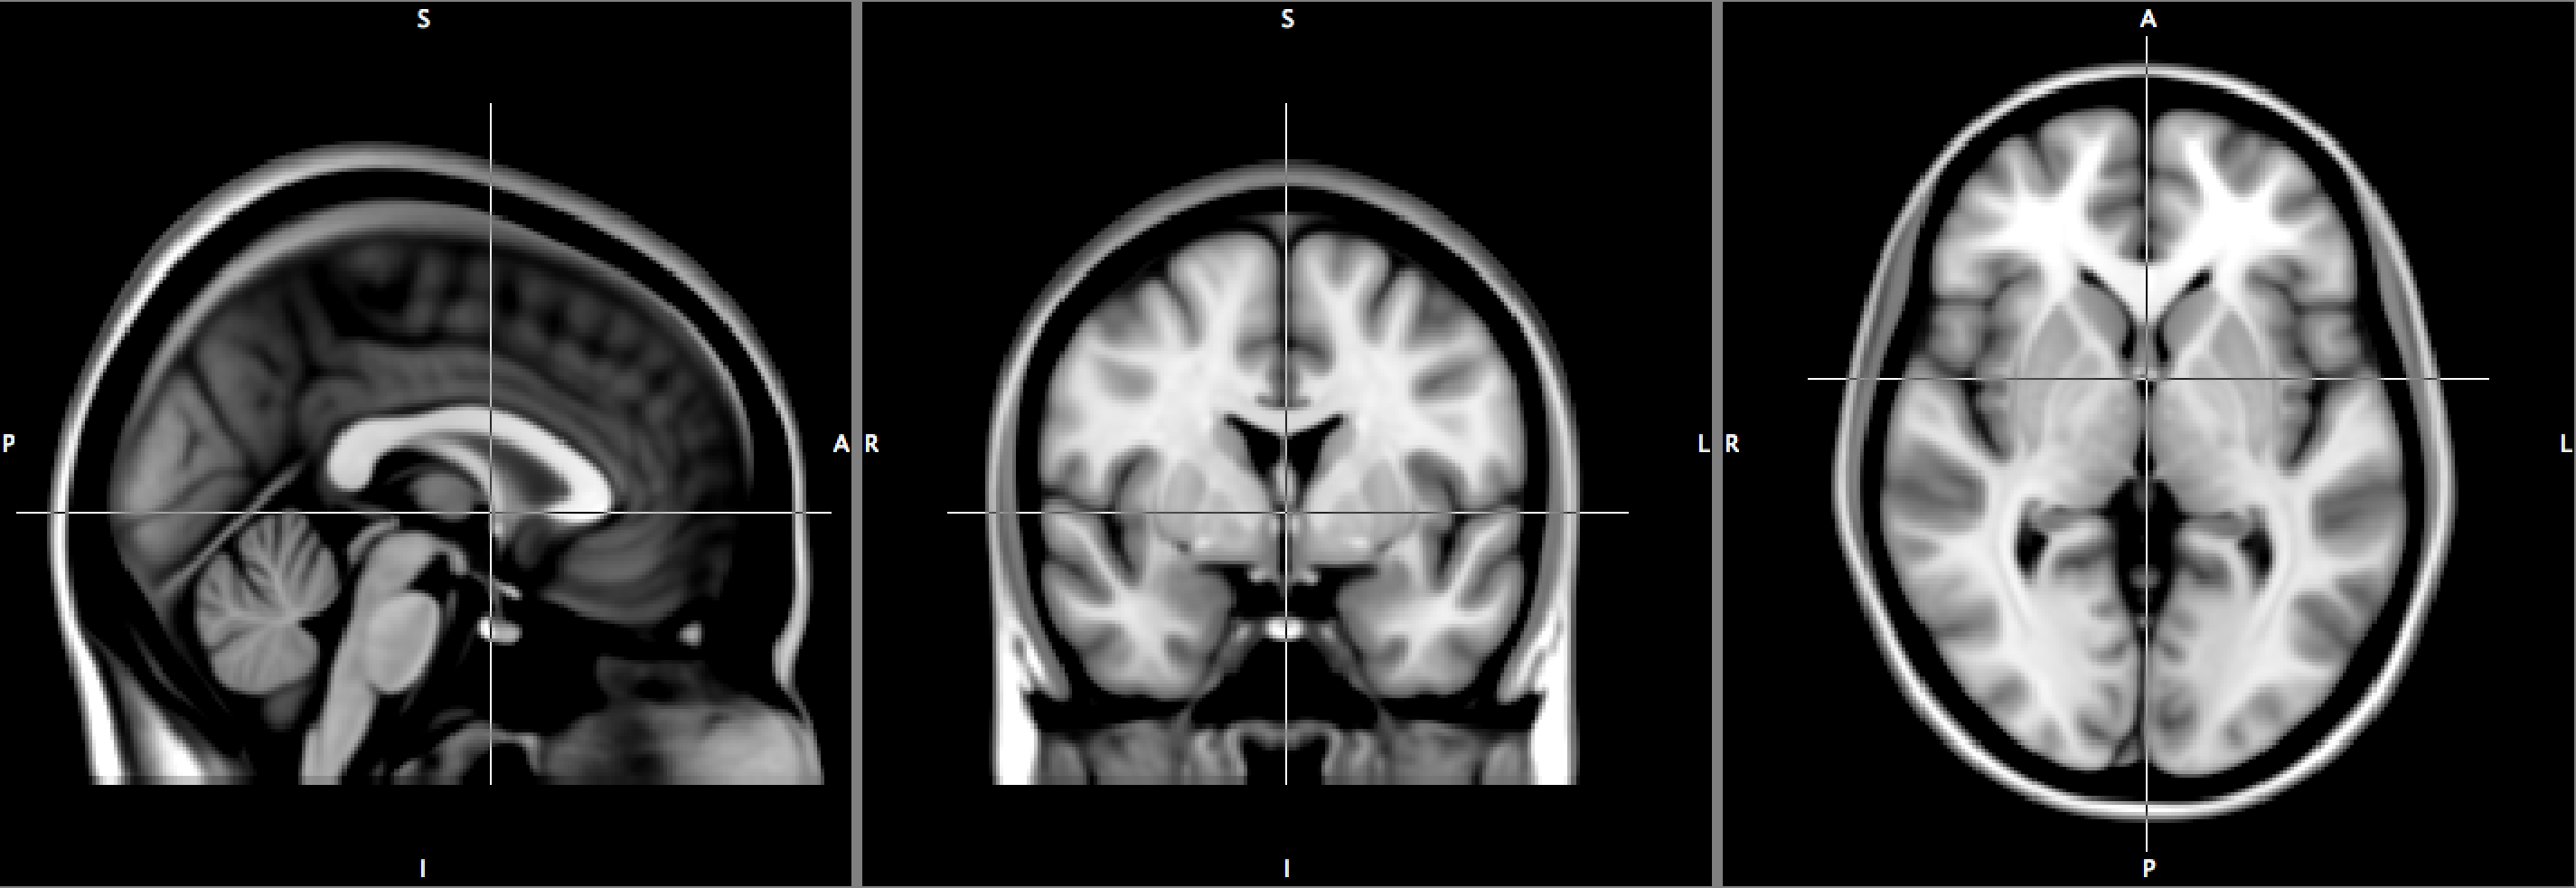

Before the raw data can be analysed, a series of preprocessing steps needs to be undertaken. These include motion correction, which accounts for movements during the acquisition, and spatial smoothing which increases the signal-to-noise ratio. To make data comparable across subjects, a crucial step is “spatial normalisation”, the process of warping all subjects to a standard brain template, or brain atlas. There are different atlases available, but essentially all authors use either the Talairach atlas (Talairach and Tournoux, 1988) or the MNI atlas (see Fig. 1).

After spatial normalisation, all subjects’ data exist in a common space. Specifically, we can assume that a given voxel corresponds to (roughly) the same region in all subjects’ brains. Statistical analysis then proceeds in a mass-univariate approach, fitting a model at each voxel independently of every other voxel. For every subject, time series regression models are fitted in each voxel, where the regression coefficients represent the effect of the different tasks. Task effects or comparisons can be made with the proper “contrasts”, meaning the estimated linear combination of parameter estimates that relates to the effect of interest. These subject-specific contrasts are subsequently analysed in a “second level” population model. The result is a 3D image of statistics, one for each voxel in the brain, measuring the evidence against the null hypothesis of no effect. The images are assessed either voxel-by-voxel, or by assessing the size of connected components, or clusters, after thresholding the image at an arbitrary threshold. See Friston et al. (2002), Mumford and Nichols (2006) and Mumford and Nichols (2009) for a detailed review of different approaches for the statistical analysis of fMRI data.